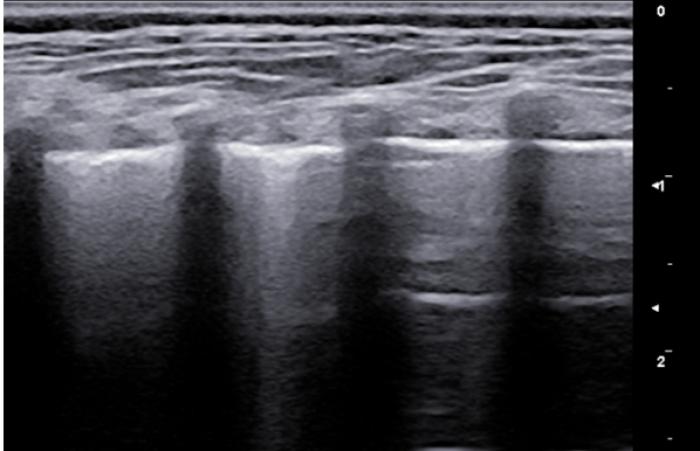

Líneas A

Son las líneas hiperecogénicas, horizontales, paralelas a la LP y equidistantes (su separación es la misma que existe entre la piel y la superficie pleural) que se van extendiendo hasta el fondo del campo ecográfico. Son fruto del reflejo del ultrasonido en el aire pulmonar, volviendo este a la sonda y creando la repetición de dicha superficie (reverberación).

Son visibles en todo pulmón bien ventilado, pero también estarán presentes en el neumotórax por lo que en este punto es vital observar el deslizamiento de la LP para su diferenciación (Figura 3A-B).